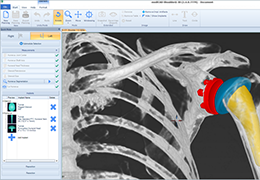

Visualization Tools

Parametric and non-parametric statistical maps may be superimposed both on the original functional scans as well as onto T1-weighted 2D or 3D anatomical reference scans. Time courses of selected regions-of-interest (ROIs) are available both in 2D and 3D representations. Statistical maps may be computed either in the 2D or 3D representation since structural as well as functional 4D data (space x time) are transformed into Talairach space. This allows you to compare activated brain regions across different experiments and across different subjects

Segmentation

Segmentation of tissue (e.g., isolating the brain, differentiating gray and white matter) is performed using region-growing methods, filter operations as well as the application of 3D templates. Using the mouse it is very easy to explore a 3D volume with superimposed pseudocolor-coded statistical maps in a four-window representation showing a sagittal, coronal, transversal and oblique section. Based on a (segmented) 3D data set a three-dimensional reconstruction of the subjects' head and brain can be calculated and displayed from any specified viewpoint using volume or surface rendering.

Mesh Manipulation

Fast and interactive surface slicing, cortex inflation and unfolding in real-time.